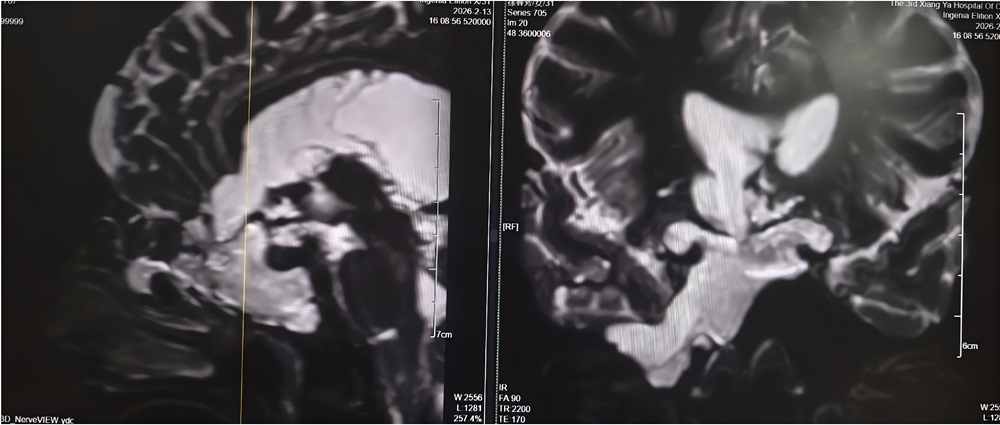

4年前,刘女士开始出现鼻腔流血、反复清水样流液,并伴有嗅觉减退。期间,她曾辗转多家医院及诊所就诊,医护人员多以“炎症”为病症进行对症治疗,但症状始终未得到根本改善。此后,刘女士多次出现发热伴鼻腔流液的情况,却一直未能明确病因,病情反复迁延。2026年2月11日,刘女士病情突然恶化,突发高热,体温超过39℃,并出现神志模糊的症状。当地医院紧急诊断后,确诊其为“脑脊液鼻漏合并颅内感染”,并下达了病危通知。危急时刻,家属紧急将刘女士转送至湘雅三医院功能神经外科求治,寻求进一步救治。 刘女士入院后,湘雅三医院功能神经外科杨靓副主任医师团队第一时间为其完善影像及实验室检查。经系统评估与综合分析,专家团队明确诊断刘女士所患疾病为——与脑室相通的高流量脑脊液漏,且其颅内感染情况较为严重。

2月14日,杨靓主任团队为刘女士实施“脑室—腹壁外引流术”,通过手术将其颅内感染的脑脊液引流至体外,同时联合规范的抗生素治疗,双管齐下控制感染。据悉,脑室—腹壁外引流术是一种临时的微创脑脊液引流手术,可快速降低颅内压力、廓清感染脑脊液,为后续根治性手术创造条件。经过持续引流和脑脊液更新,刘女士的感染症状迅速得到控制,体温逐渐恢复正常,意识也逐步清醒,病情趋于平稳。2月26日,在确认刘女士颅内感染完全控制、身体条件达到手术标准后,杨靓主任团队为其开展经鼻内镜脑脊液漏修补术。术中,专家团队借助高清内镜的精准视野,准确定位漏口位置,同时从刘女士大腿取少量自体组织,为其完成多层严密修补,实现精准“堵漏”。据了解,经鼻内镜脑脊液漏修补术具有创伤小、恢复快、并发症少的优势,已成为脑脊液鼻漏修补的优选方式之一。 术后第一天,刘女士鼻腔清水样流液的症状便完全消失,困扰其多年的头痛也明显缓解。经过后续规范的护理与康复治疗,刘女士身体恢复良好,于3月初顺利出院,彻底摆脱了困扰4年的病痛。